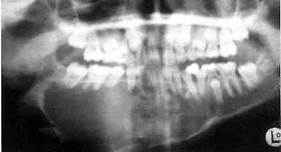

Рентгенологическая картина. Различают три формы остеокластомы. Ячеистая форма представлена множеством мелких полостей, разделенных костными перегородками. При кистозной форме наблюдается очаг разрежения с чет­кими границами. Литическая форма опухоли, представлена бесструктурным очагом разрежения и лизисом корти­кальных пластинок. Возможна промежуточ­ная картина ячеистой и кистозной разновидностей опухоли.